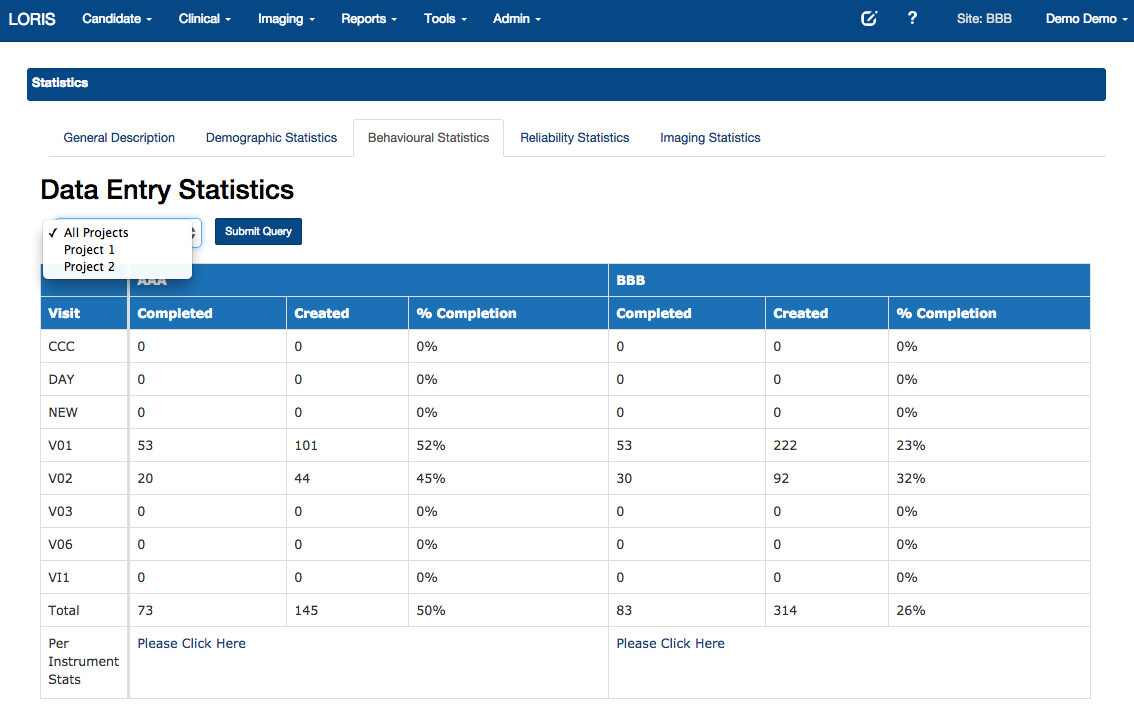

Summary Statistics

LORIS summary statistics

- Summary Statistics - Demographics, imaging, data entry

Data Querying Tool - Statistics